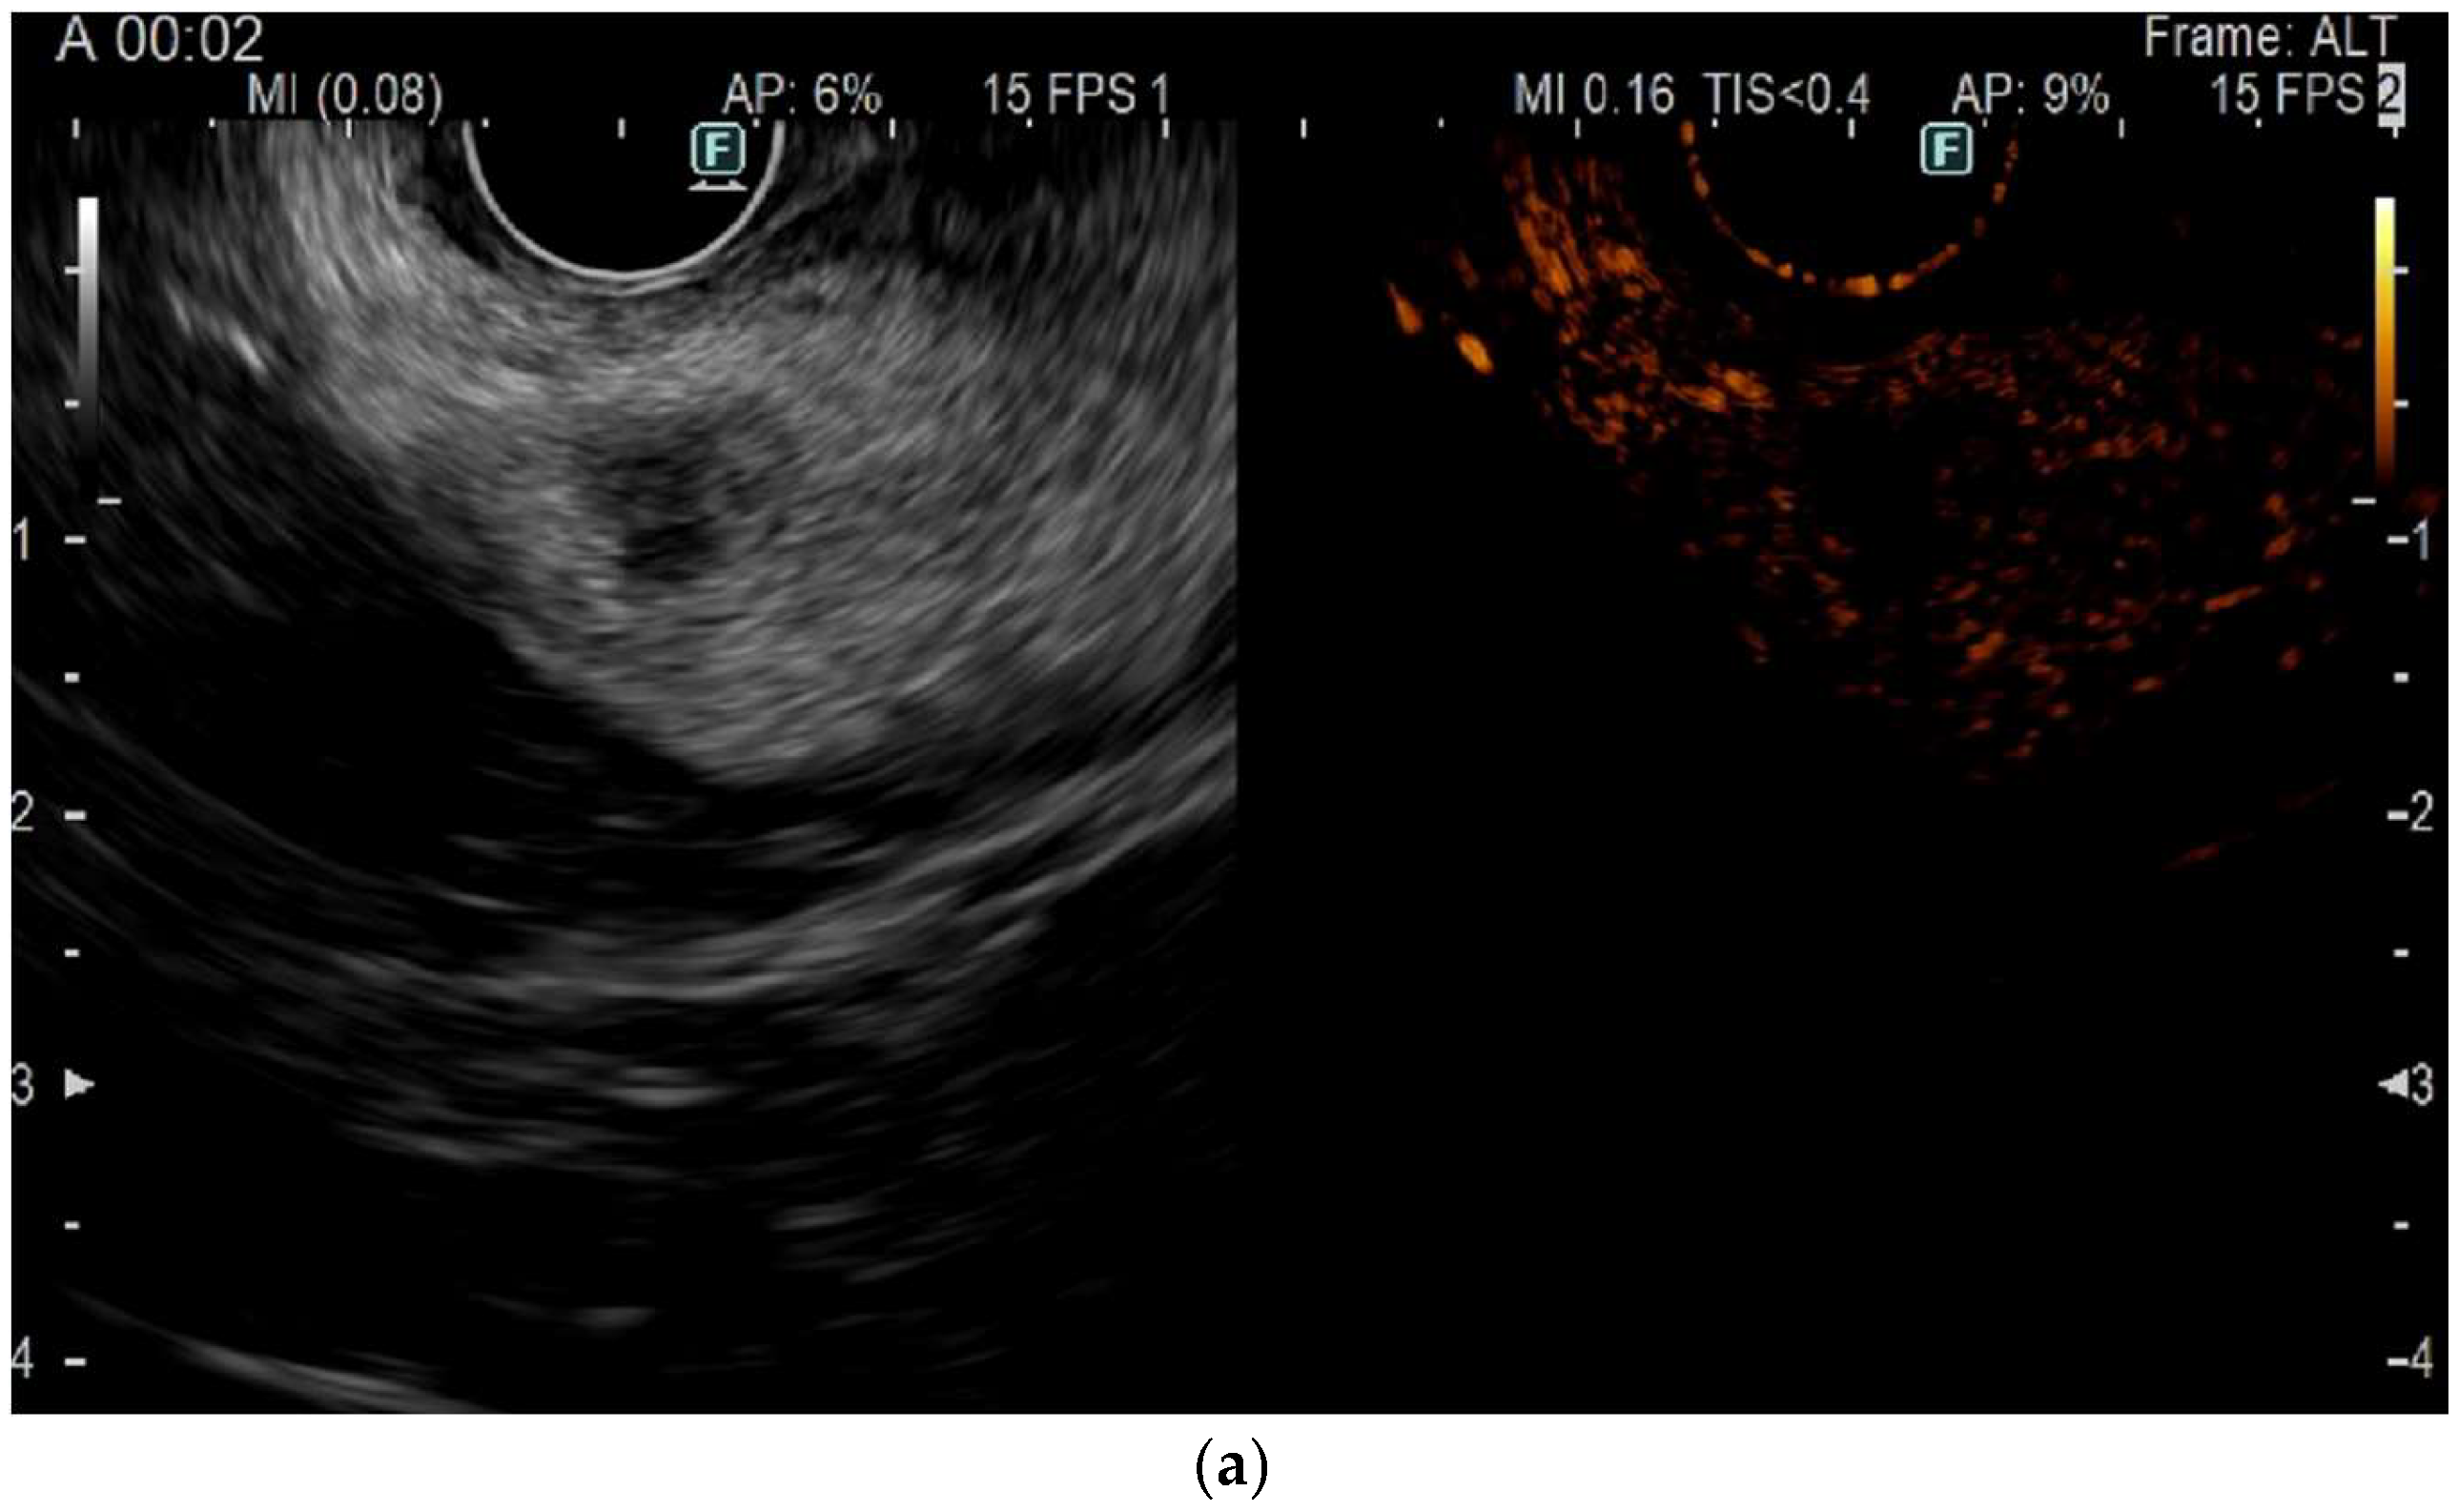

3.3. Role of Contrast Harmonic EUS (CH-EUS) and Follow-Up

- Choi, J.-H.; Seo, D.-W.; Song, T.J.; Park, D.H.; Lee, S.S.; Lee, S.K.; Kim, M.-H. Utility of Contrast-Enhanced Harmonic Endoscopic Ultrasound for the Guidance and Monitoring of Endoscopic Radiofrequency Ablation. Gut Liver 2020, 14, 826–832. [Google Scholar] [CrossRef]